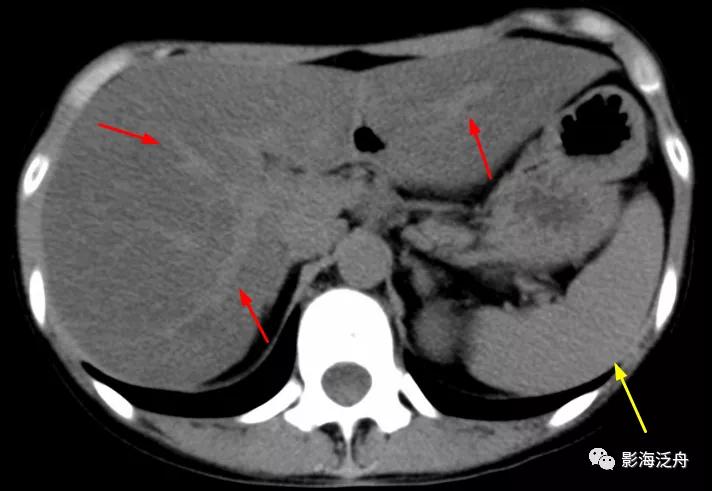

年轻女性,重度脂肪肝患者,平时喜食甜食及奶茶。

CT平扫上可见肝实质密度弥漫性减低,低于同层面脾实质密度(黄箭),肝内血管呈相对高密度影(红箭)。